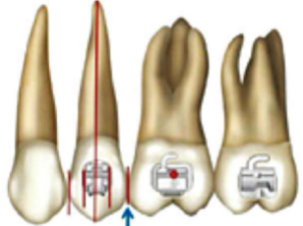

2、双尖牙的托槽要与牙长轴一致,垂直向位置应该在临床冠中心偏向龈方(图3,图4)。

2、试带环的时候,不要选择过紧的带环,带环太小无法在磨牙牙冠上做调整;带环也不能太大,不要指望用粘结剂充填过大的带环和牙冠空间,过大的带环在矫治过程中很容易脱落。要保证带环的颊管位置应该在磨牙牙冠的临床冠中心,带环颊管的近中边缘应与磨牙的近中颊尖中央脊对齐,颊管与磨牙近远中颊尖连线平行(图7)。

3、颊面管的粘结定位为第一磨牙的颊面管应位于牙齿的临床冠中心,与磨牙近远中颊尖连线平行,上颌第二磨牙的颊面管位于临床冠中心偏颌方0.5mm。如此可以保存上颌磨牙后部的补偿曲线(图8,图9)。